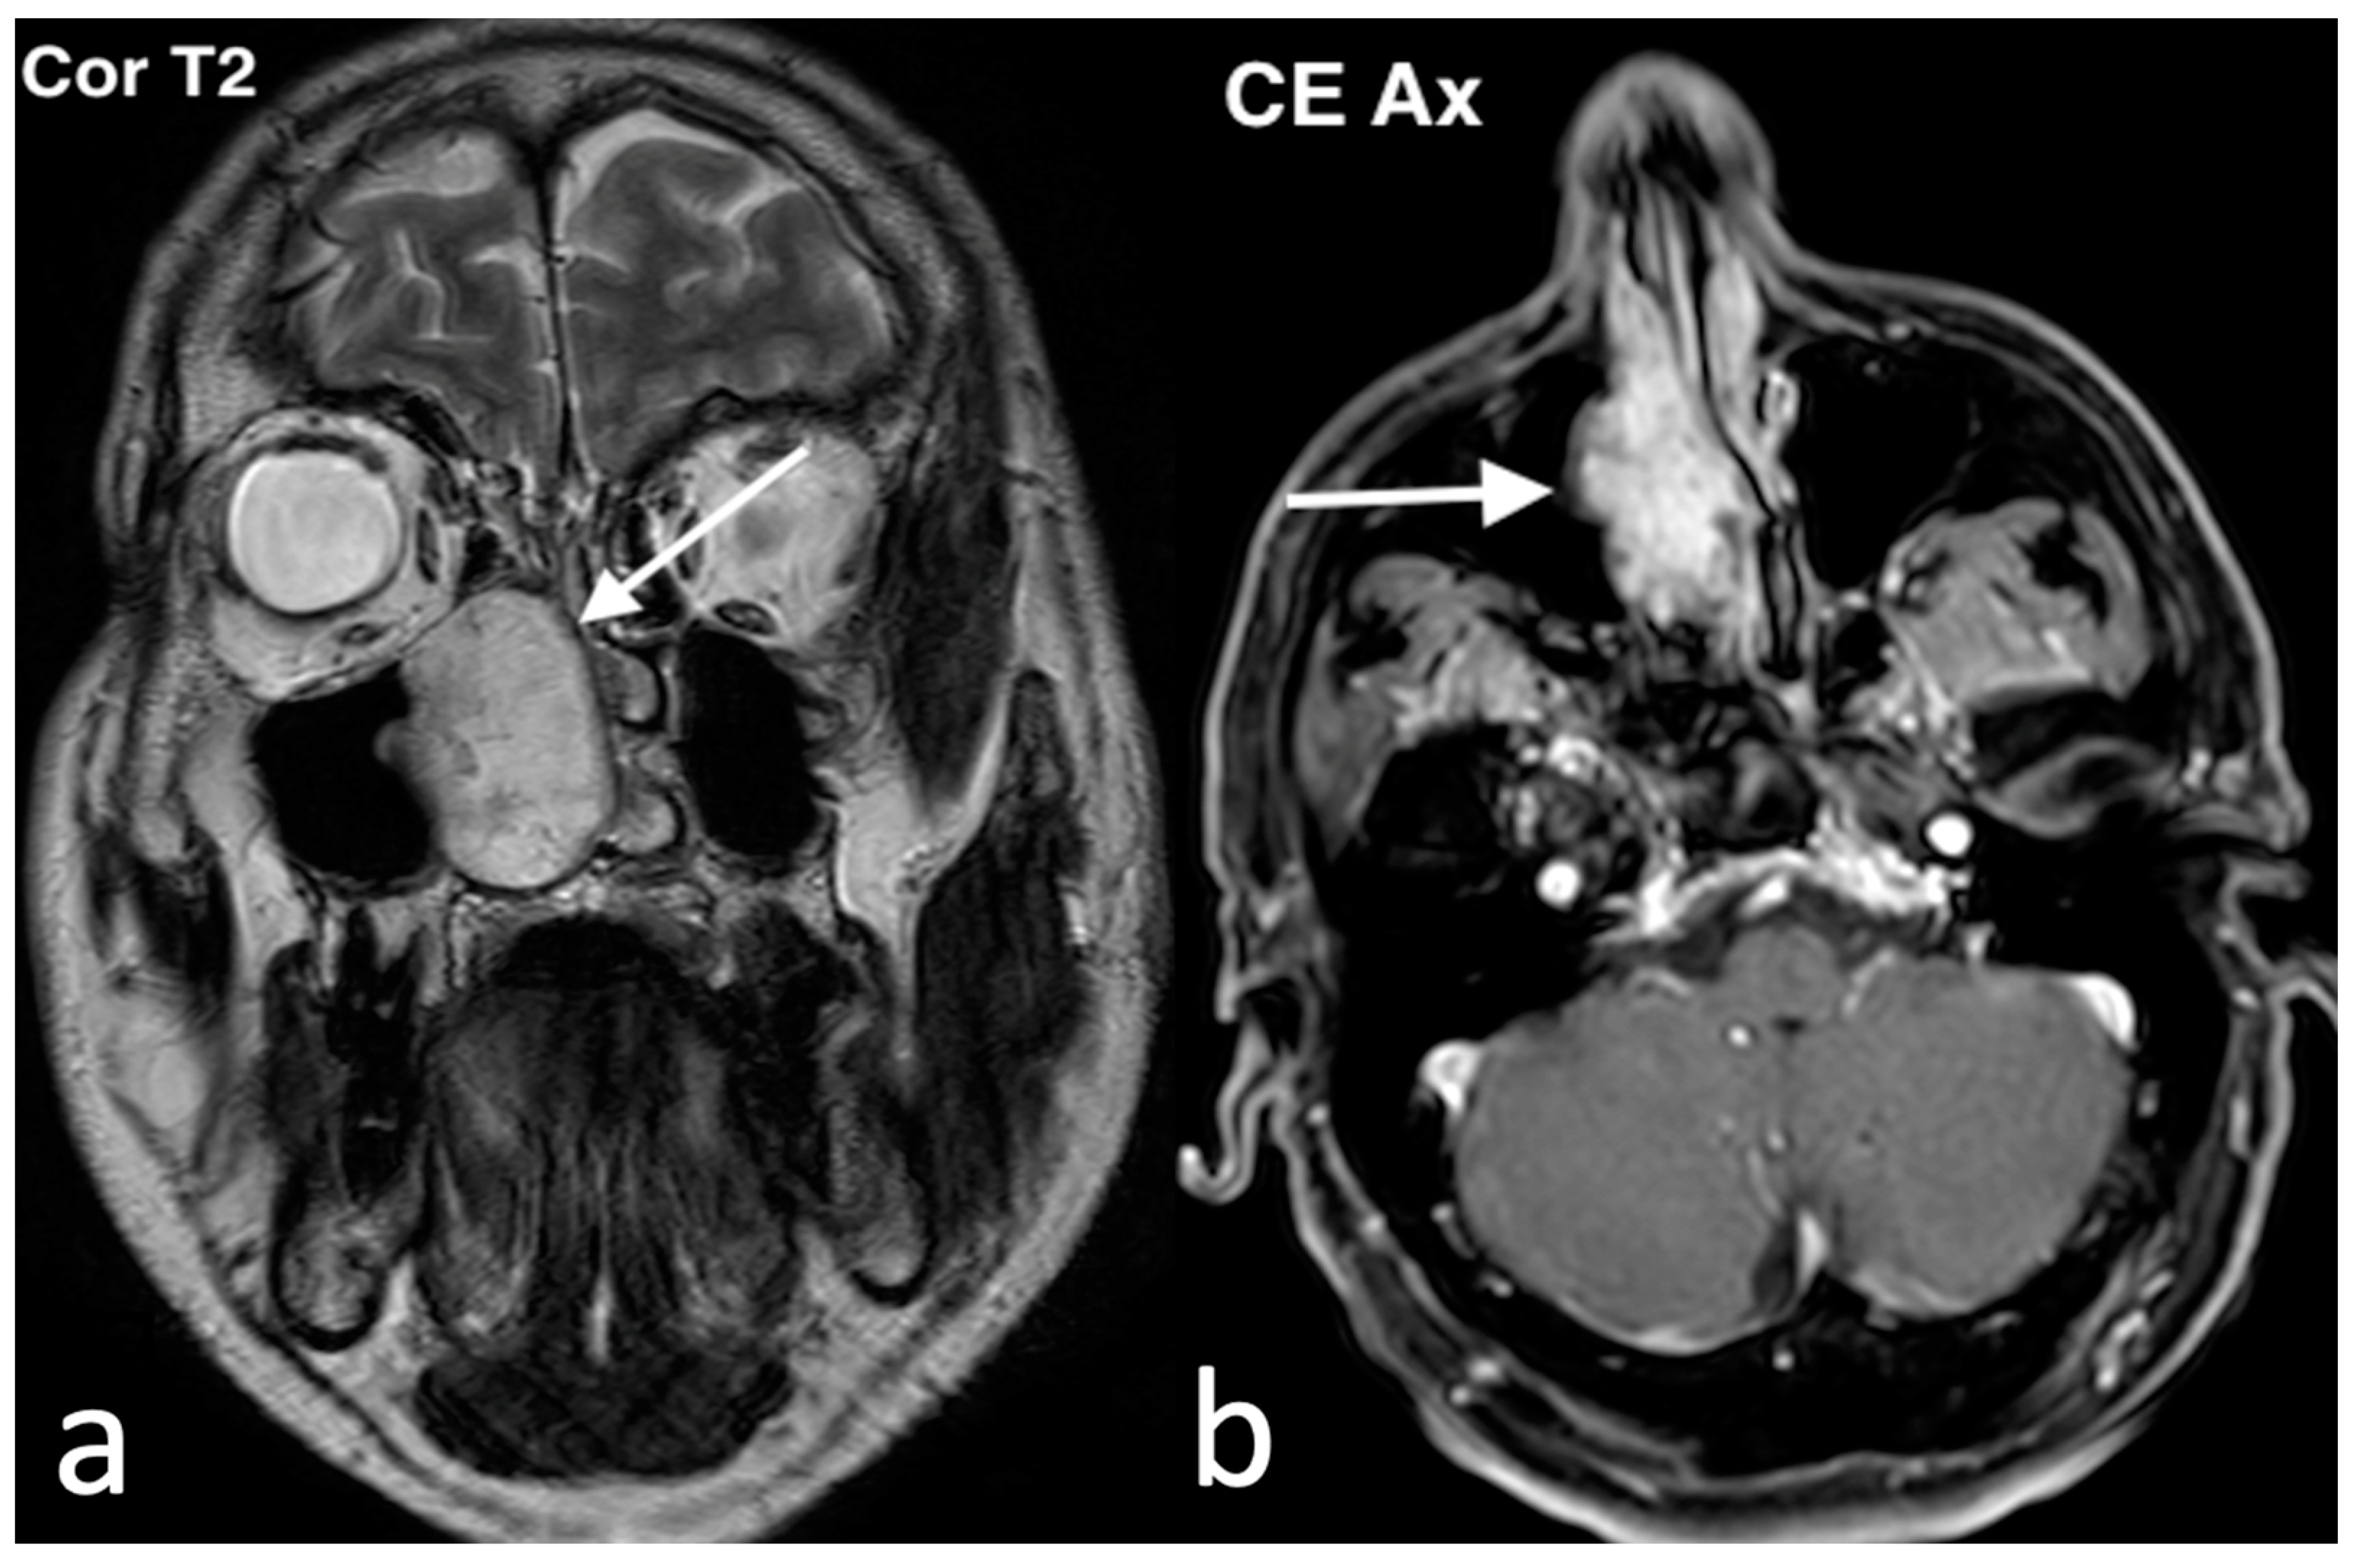

3.3.1. Non-Hodgkin Lymphoma

3.3.2. Esthesioneuroblastoma